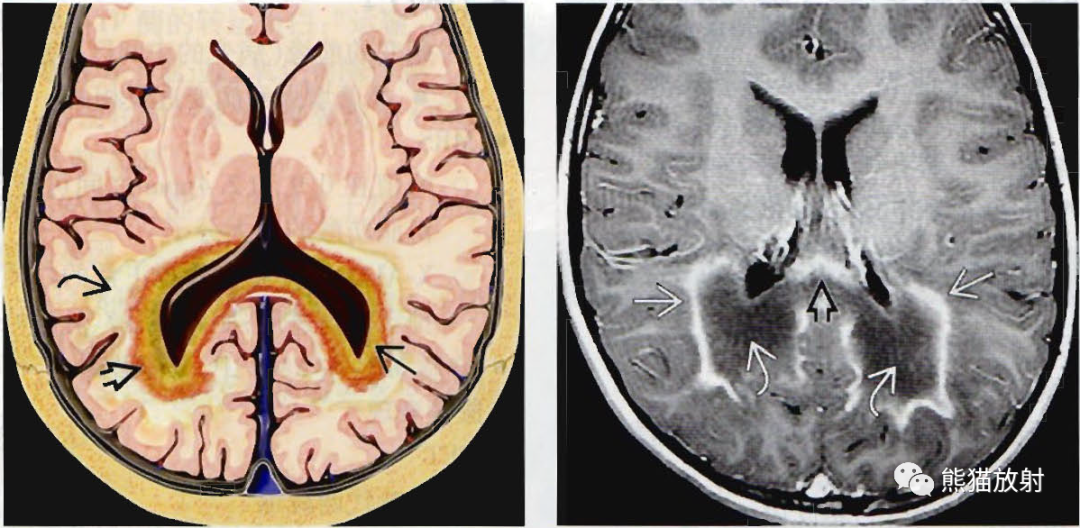

(左) CCALD患者(ALD1型) ,轴位FLAIR MR显示内侧膝状体(弯箭)、颞枕叶的脑室周围和深部白质(空箭)呈高信号;

(右)同一位CCALD患儿,轴位FLAIR MR显示呈高信号的穹隆后柱(黑弯箭)、胼胝体压部(黑直箭)、多分层受累的三角区周围白质(黑空箭)和外囊/最外囊(白弯箭)。